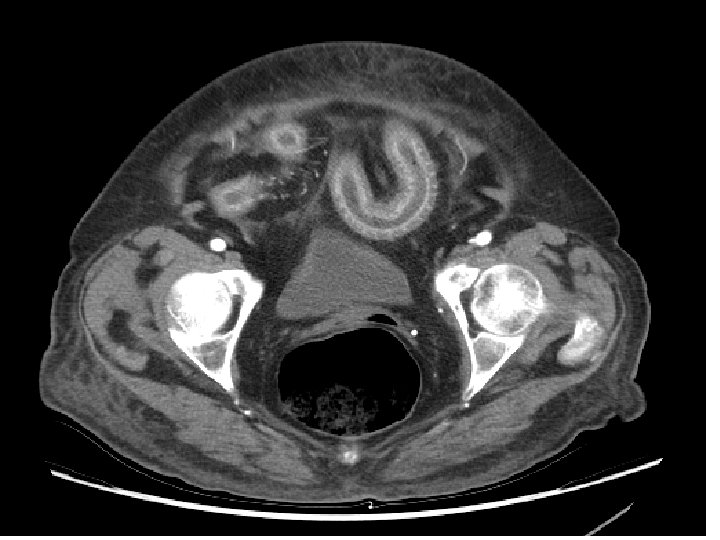

Siguiendo el consejo del radiólogo de guardia, se practica TC (NO angio-TC) Y los datos aportados no son los clínicos, sino el informe ecográfico

Informe TC • Segmento largo de asa ileal en FID-hipogastrio con engrosamiento transmural concéntrico. • Íleon terminal respetado. • Sin afectación de grasa mesentérica adyacente. • No se aprecia líquido libre, colecciones abdominales ni aire ectópico. • Calcificaciones ateromatosas aortoilíacas y en arterias viscerales. • Se plantea diagnóstico diferencial entre enteropatía inflamatoria e isquemia intestinal.

Sobre este informe… • Había suficientes datos CONTRA la E. I. I. : – la edad (la EII de inicio en ancianos es extremadamente rara) – la afectación segmentaria continua; – la preservación del íleon terminal; – la no afectación de grasa mesentérica

Sigamos… • Había datos a favor de la isquemia: – nuevamente la edad (somos médicos, no fotógrafos); – las calcificaciones en aorta; – y, sobre todo, las calcificaciones en arterias viscerales. • Al menos, se sugirió el diagnóstico.